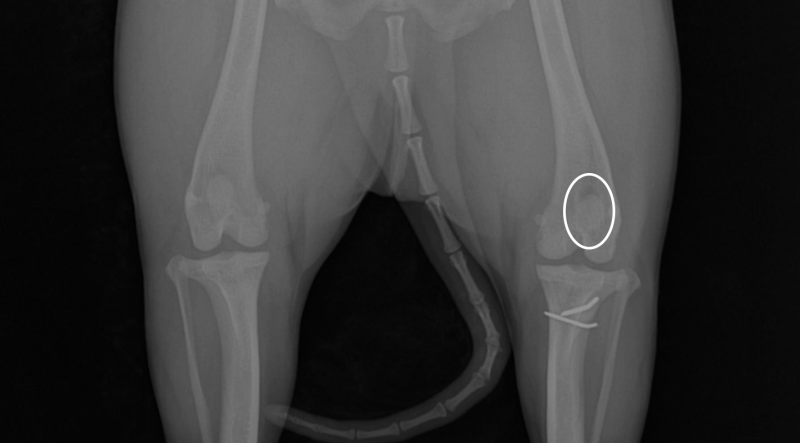

환자의 슬개골 사진입니다.

두 달 전, 수술한 왼쪽 슬개골은 잘 유지되고 있는 모습이 확인됩니다.

당장 아파하는 오른쪽 다리는 방사선 상으로 정상 위치에 확인되나, 빠졌다 들어갔다 하는 상태였습니다.

환자는 오른쪽 다리 슬개골 탈구 2단계를 진단받았고, SD동물의료센터/메디엘동물병원에서 수술 일정을 다시 잡게 되었습니다.